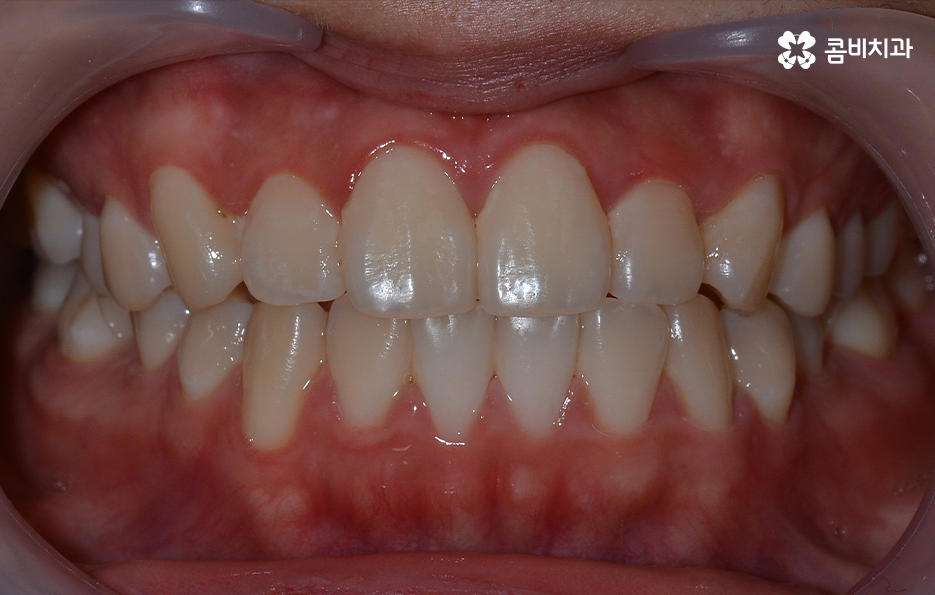

출처 아카이브 열기치아교정의 목적은 다양하지만 돌출입을 개선하고자 하는 목적성을 갖는 경우 발치가 필요한 경우가 대부분이라고 할 수 있는데요. 그 이유는 입이 나와 있는 돌출입을 개선하기 위해서는 앞니 부분이 뒤 쪽으로 들어가야 돌출입이 개선되기 때문인데 치아를 안쪽으로 이동시키기 위한 공간 확보를 위해 발치가 필요한 경우가 많은 거예요.

돌출입을 개선하기 위한 교정 치료의 사례에도 돌출입발치교정 사례가 많은 이유도 치아의 발치를 통해 앞니를 후방 이동시키는 치아 교정의 원리가 있기 때문이라고 설명할 수 있어요

이처럼 치열의 변화는 얼굴형 변화에도 많은 영향을 줄 수 있기 때문에 치아교정의 만족도는 치열뿐 아니라 환자 개개인의 골격과 얼굴형을 고려하여 잘 어울리는 조화적인 측면과 치아의 건강 등 고려해야 할 점이 많다는 것을 알 수 있는데요

오늘은 돌출입발치교정 통해서 치열도 가지런하게 교정하고 얼굴형의 변화뿐 아니라 교합까지 잘 맞물려서 건강하게 치아교정을 하는 방법에 대해 알아볼 거예요